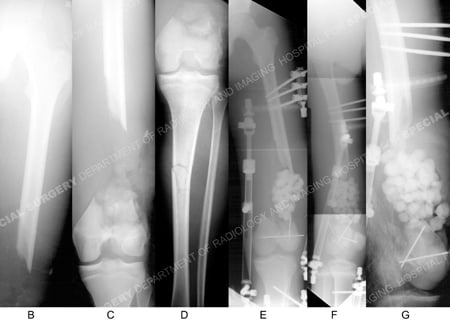

X-rays (3 images on left) illustrating an AO/OTA Type C3.3 distal femur fracture with segmental bone defect and an ipsilateral tibial shaft fracture; (3 images on right) anteroposterior and lateral radiographs following placement of external fixation and antibiotic beads at the site of the segmental bone defect.